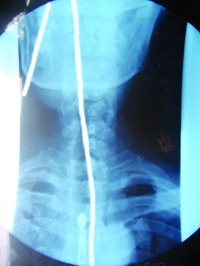

2007年3月29日,天蚕神功第14代传人傅英杰在福建电视台“发现档案”记者见证下表演了天蚕神功用鼻子吊起14.75公斤水,而且将表演的细绳吸入鼻孔到胃中共67厘米,还将一辆1458公斤重面包车拖出13米远的距离。X光胶片上能清晰反映出傅英杰的确将细绳吸入胃内,他的鼻孔、舌根、咽喉、食道、胃部贲门有长期磨擦用力留下的痕迹。傅英杰自幼随父练习天蚕神功,功底深厚。现扎根石狮,面向全国,弘扬中华武术文化。